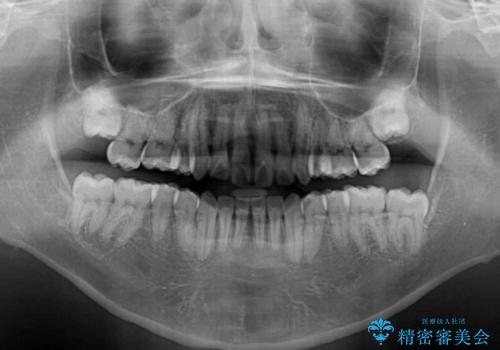

- 学生時代に抜歯矯正した歯列が後戻りしてきたとのことで来院された患者様です。

舌の突出癖が原因で上顎前歯が前方に移動したと考えられたため、舌のトレーニングを徹底して行っていただきながら、後戻りを解消していくこととしました。

ワイヤー矯正ということで、上顎大臼歯を後方に移動するための補助装置を併用して、積極的に前歯を引っ込めていくこととしました。

上顎歯列全体がスムーズに後方移動でき、1年で治療を終えることができました。